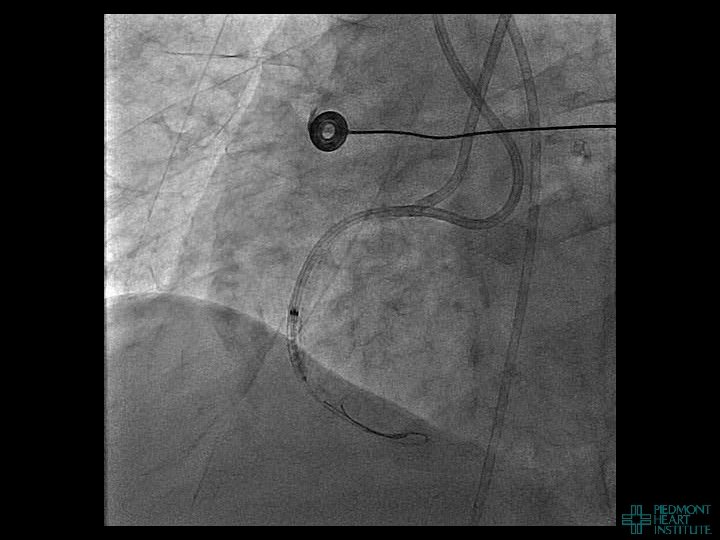

Case Example 2